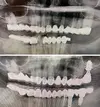

Implant tedavisi